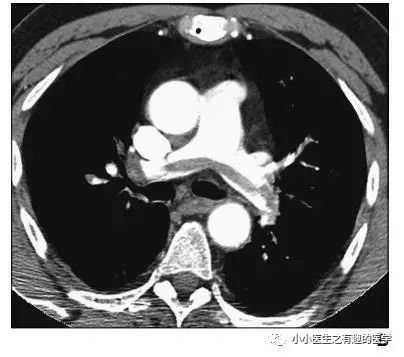

翠花上菜,学者上图。

发现嫌疑犯,立即逮捕。

增强CT对比,一目了然。

上面的患者,增强CT放大了。